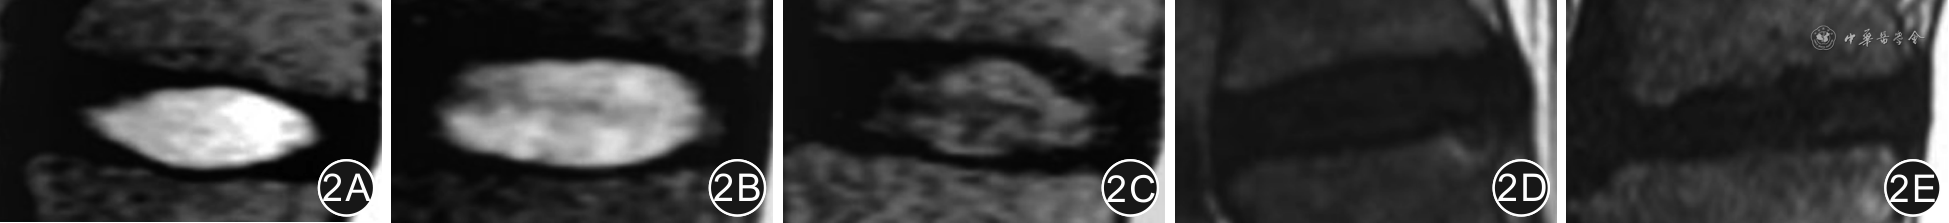

基于腰椎MRI表现,采用Pfirrmann分级标准[11],将腰椎间盘退变分为5级:Ⅰ级,髓核呈高信号,信号均匀,椎间隙高度正常;Ⅱ级,髓核呈高信号,信号不均匀,有或无水平方向低信号条带,椎间隙高度正常;Ⅲ级,髓核呈灰色,信号欠均匀,椎间隙有或无轻度狭窄;Ⅳ级,髓核呈低信号,信号不均匀,与纤维环分界模糊不清,椎间隙出现轻度或中度狭窄;Ⅴ级,髓核呈无信号的黑色,椎间隙重度狭窄。见图2。